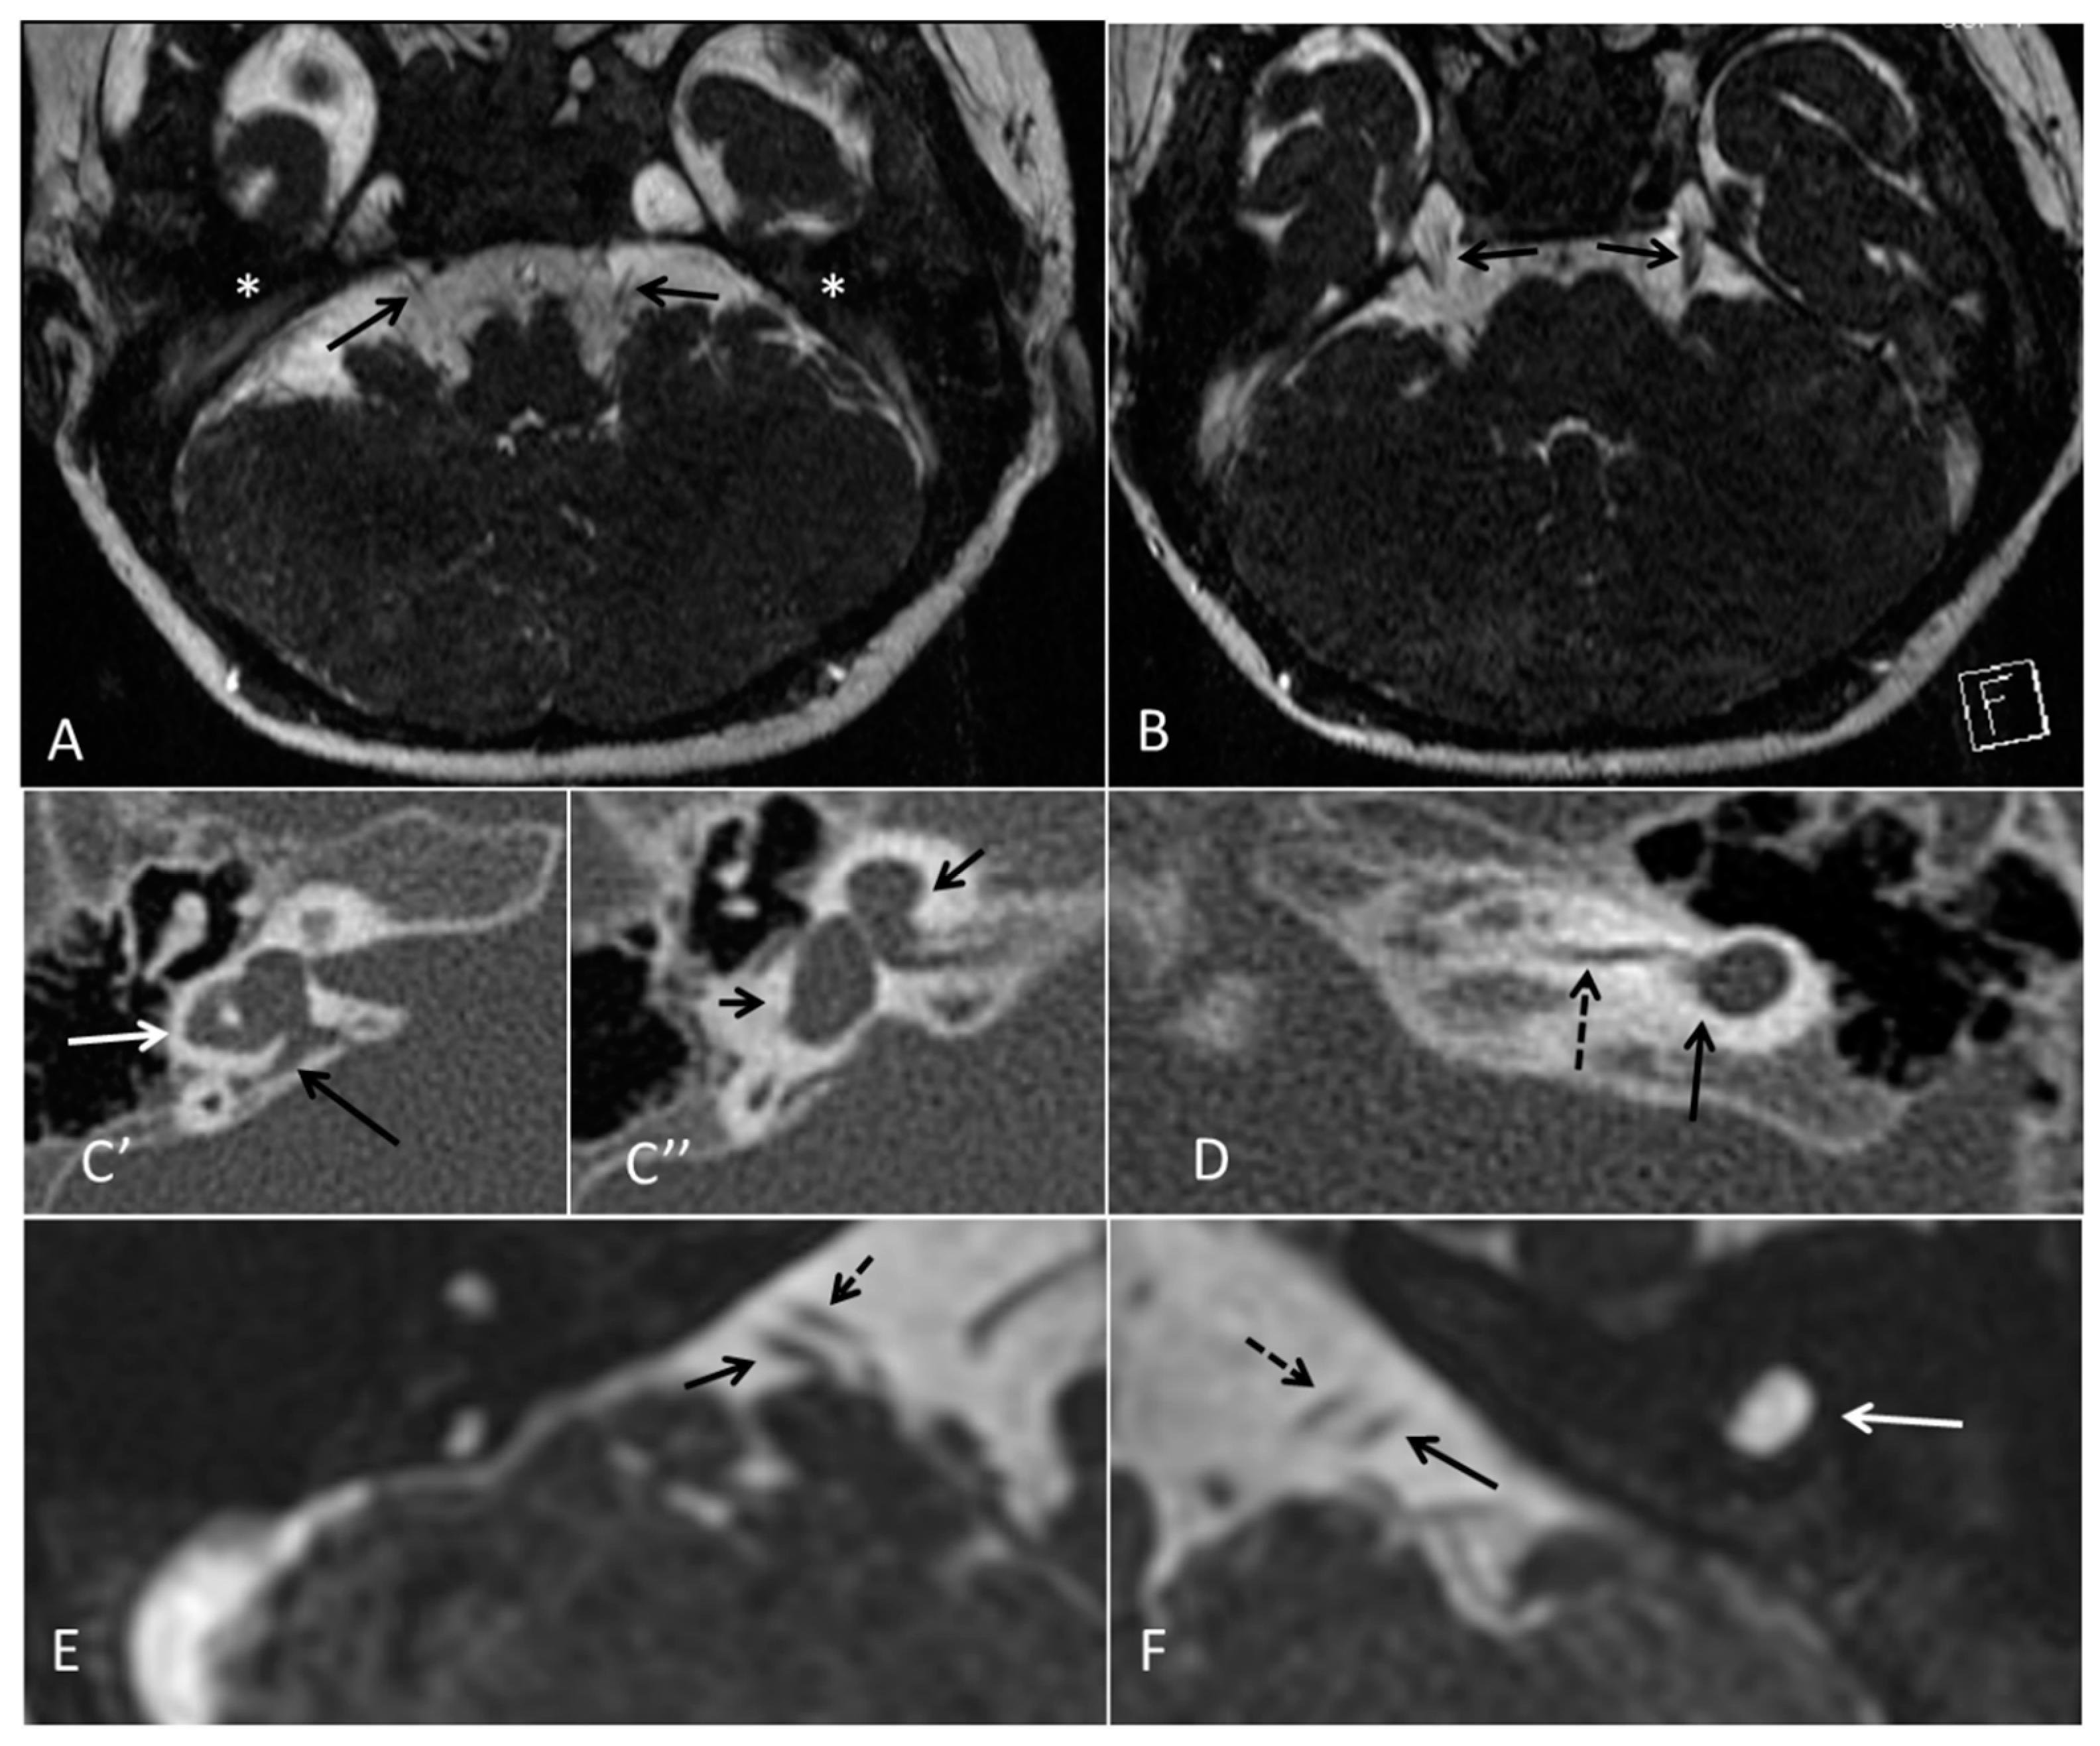

| Inner ear MRI features | Michels | Michels | Michels | L- otocyst rudimentary, R- Michel aplasia | Michels | L- Michel aplasia R- otocyst rudimentary | L- cystic vestibule R- cystic cochleovestibular malf | Michels, normal middle ear development | Michels | Michels | Michels | Michels | L- Michels R- rudimentarl cystic vestibule | Two subjects with rudimentary inner ear formation unilaterally | L- rudimentary vestibular structures R- Michels | Michels, normal middle ear development | Two subjects with cochlear basal turn, vestibule and posterior semi-circular canal | Michels, normal middle ear development | Middle ear involved. Hypoplasia petrous pyramids, bilateral labyrinth and IAC dysplasia. Stapes present in female. | CT Michels aplasia bilaterally Otic vesicle remnant ectopic in left mastoid | Michels; Middle ear structures involved | Michels | Michels |

| Inner ear (a)symmetry | S | S | S | A | S | A | A | S | S | S | S | S | A | A | A index | S | A n = 2 | S | S | S | S | S | A |